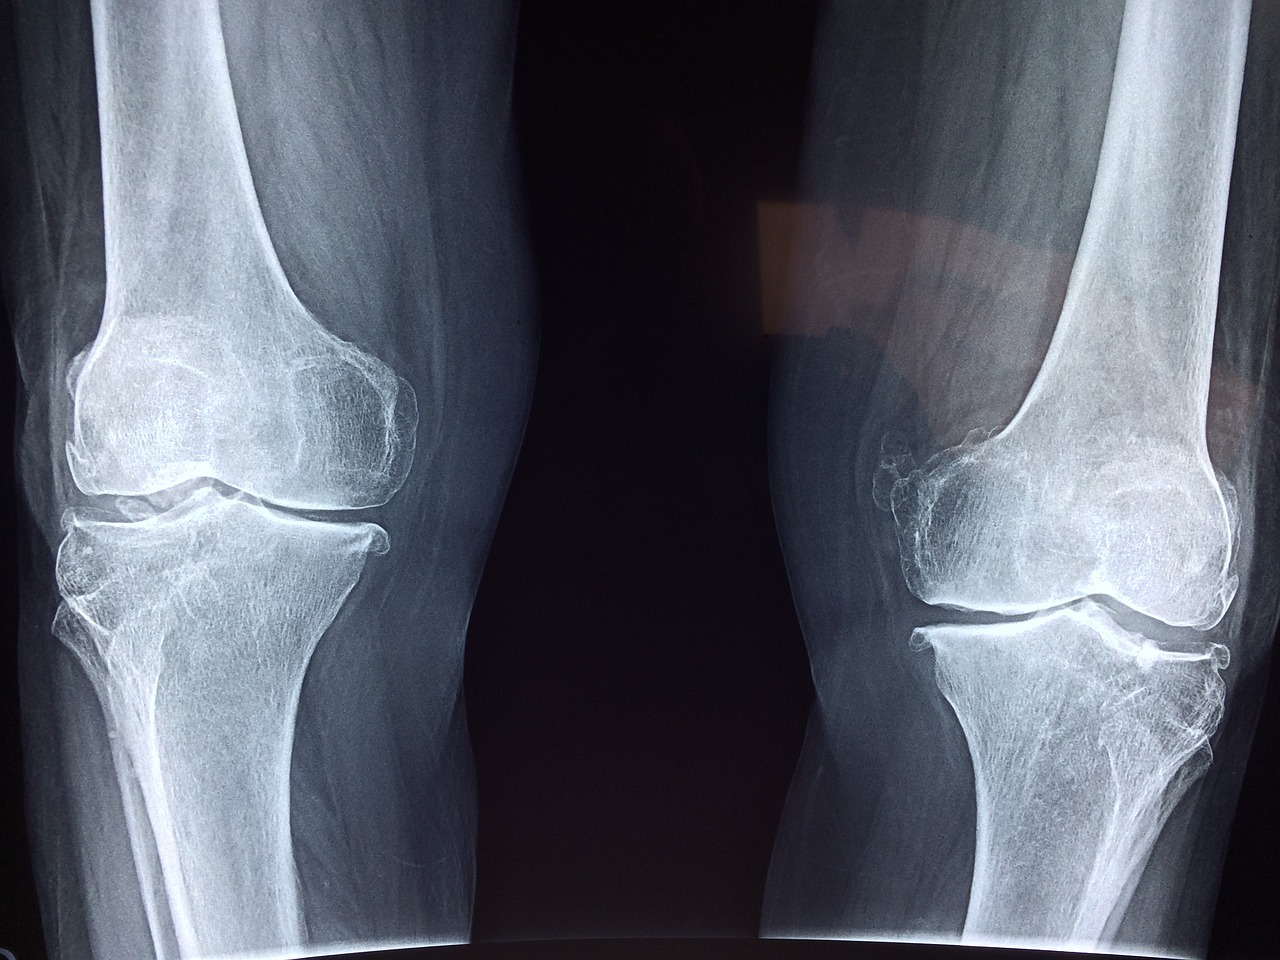

일반적으로 여러 관절에 지속적인 통증과 부종은 류마티스 관절염의 초기 증상의 특징입니다. 그리고 관절을 만지면 열감이 느껴지는 경우가 많습니다. 일반적으로 영향을 받는 관절에는 손, 손목, 무릎, 발이 포함됩니다.

류마티스 관절염은 일반적으로 신체 양쪽 관절에 대칭적으로 영향을 미칩니다. 한쪽 무릎이나 손이 영향을 받으면 반대쪽 동일한 부분의 관절에도 같은 증상이 나타날 수 있습니다. 이런 대칭적 증상은 류마티스 관절염을 다른 형태의 관절염과 구별하는 데 도움이 됩니다.